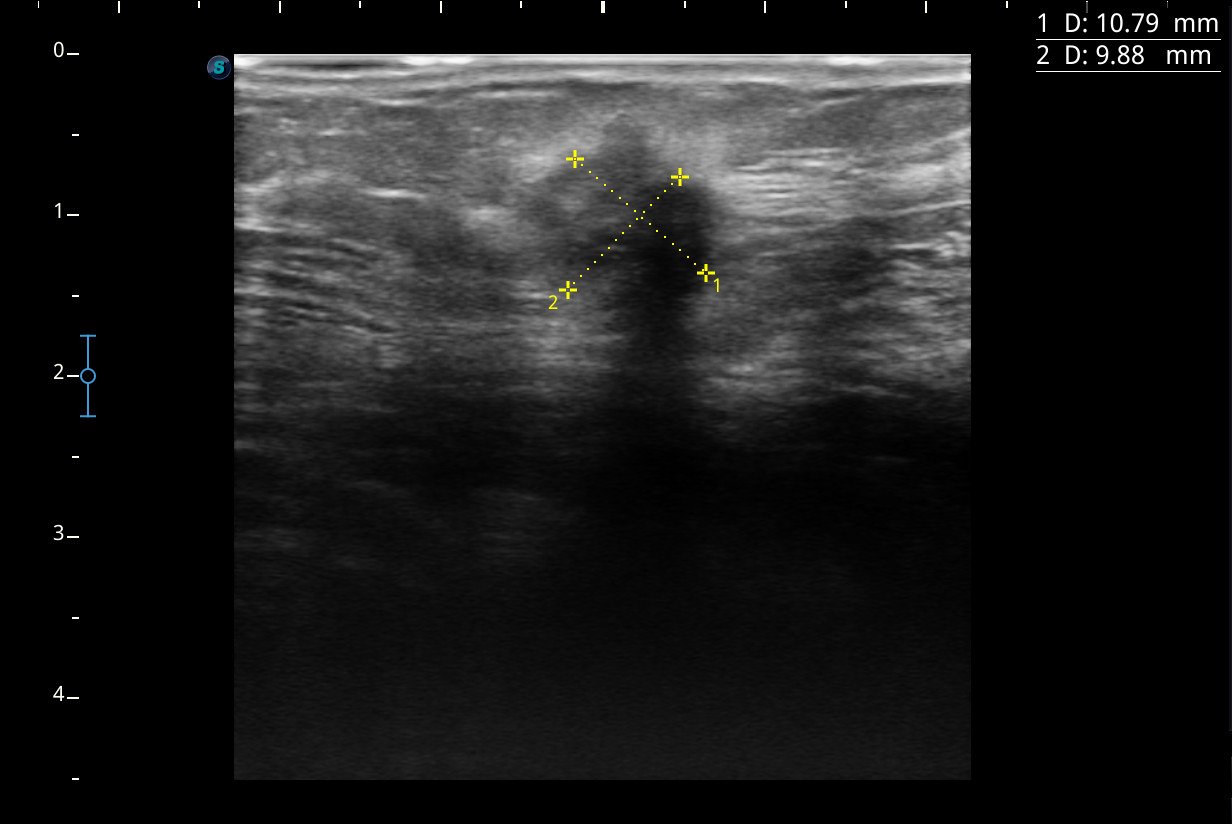

No antecedentes de interés. No traumatismo previo ni sobrecarga muscular importante. En la EF se palpa un nódulo de unos 2 cm aprox. de diámetro, molesto pero indoloro al tacto, algo duro y dudosamente adherido a planos profundos, en el CSE de la mama derecha. No bultos en axilas ni en la mama contralateral. Se realiza ecografía de mama.

Hallazgos ecográficos

Se visualiza un nódulo mal delimitado, de bordes irregulares y algo espiculados, con captación doppler color sobre todo en periferia y posibles focos centrales de necrosis, compatible con posible neoplasia.